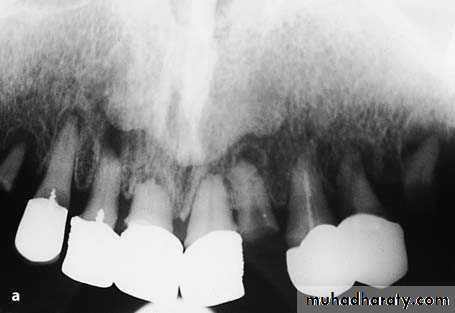

a Radiograph of maxillary teeth, after whose removal smoothing of alveolar bone is required. b Clinical photograph of teeth to be extracted